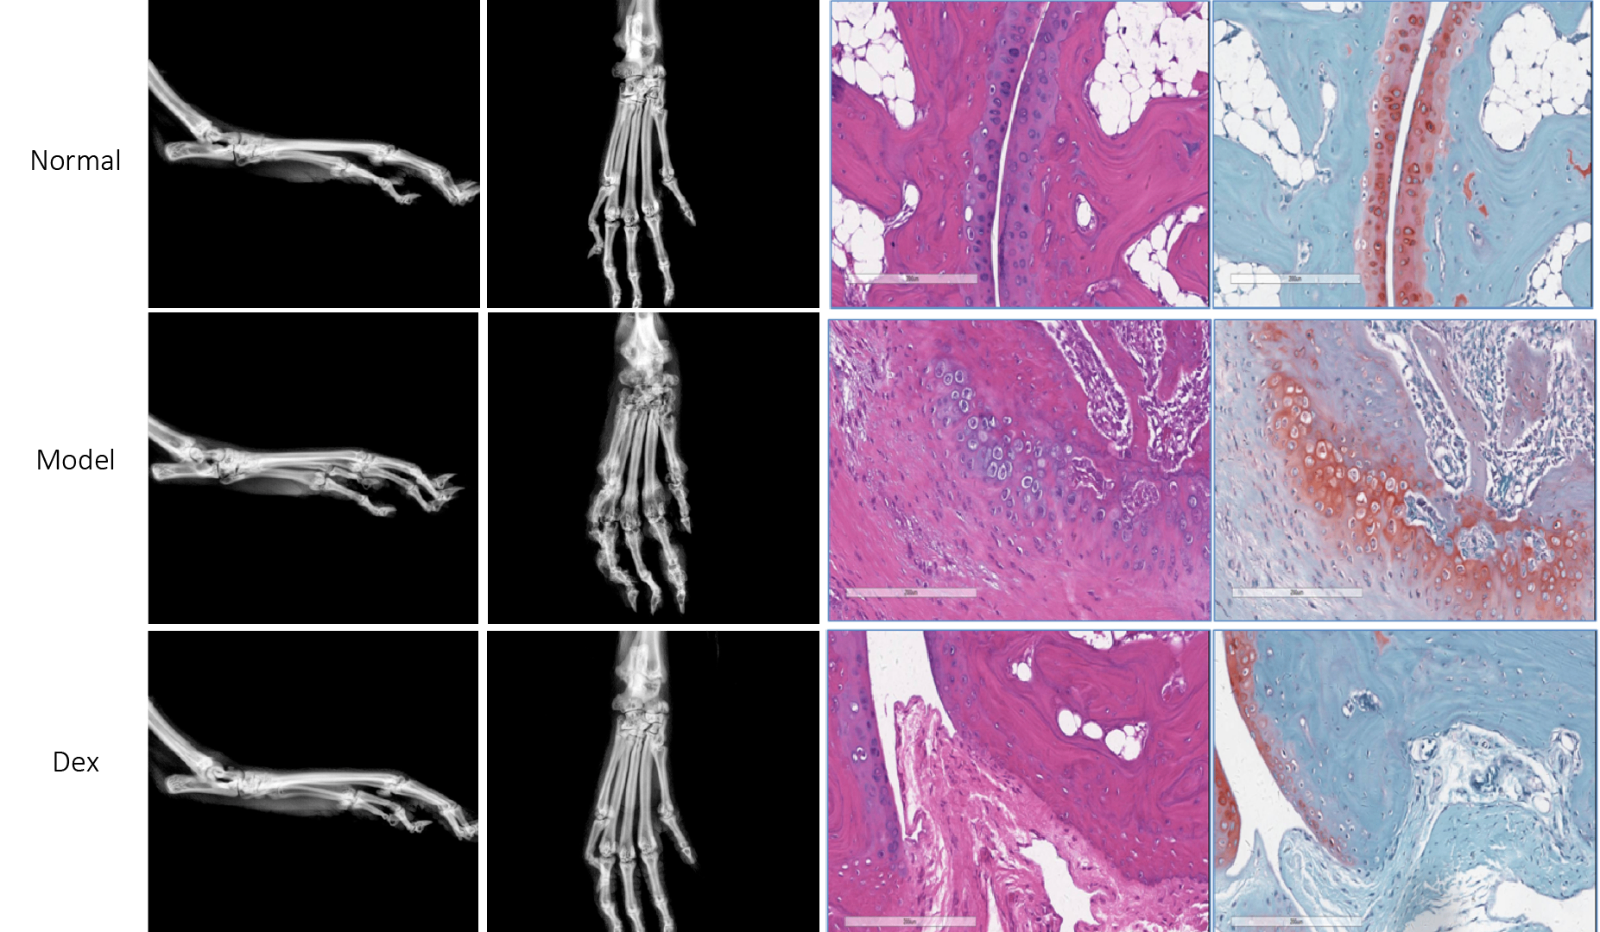

Both clinical score and joint swelling show model relevancy for RA and responsiveness to dexamethasone, an anti-inflammatory agent.

These changes can be directly observable using anatomical and histopathology observation